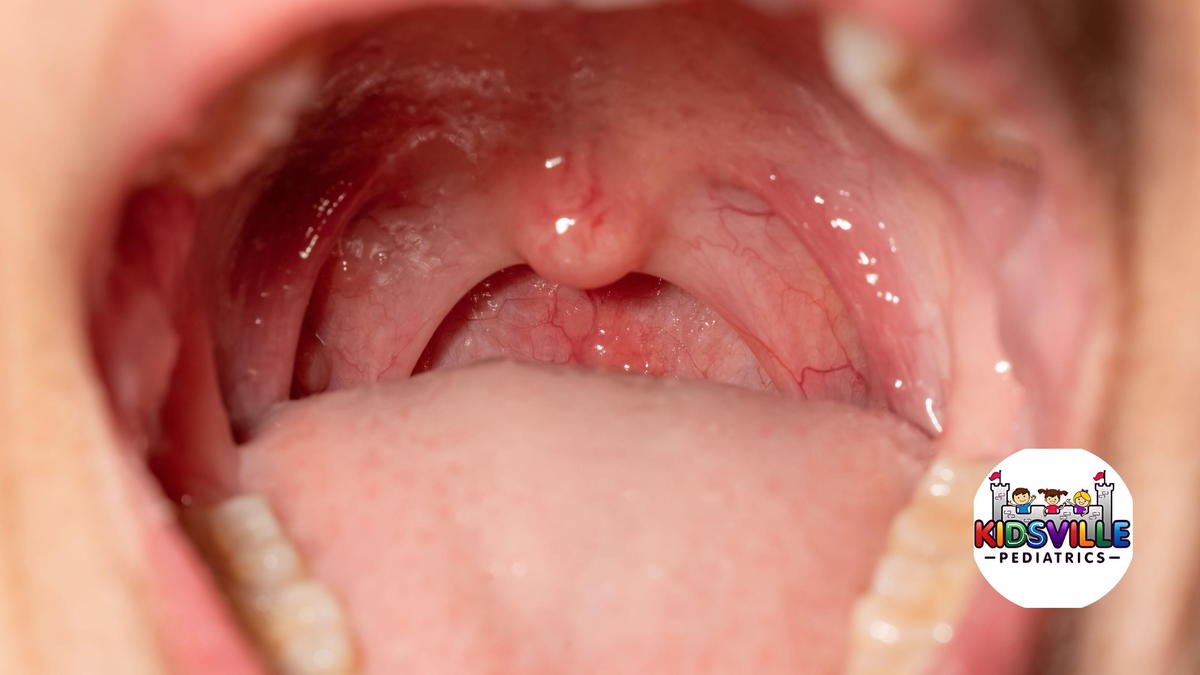

Mouth sores

In herpangina, the sores typically show up in the back of the mouth:

- Soft palate (the soft part at the back of the roof of the mouth)

- Tonsillar pillars

- Uvula (the little dangly part)

- Back of the throat

They often look like tiny gray-white blisters or ulcers with a red rim. There might only be a few, or there can be a cluster.